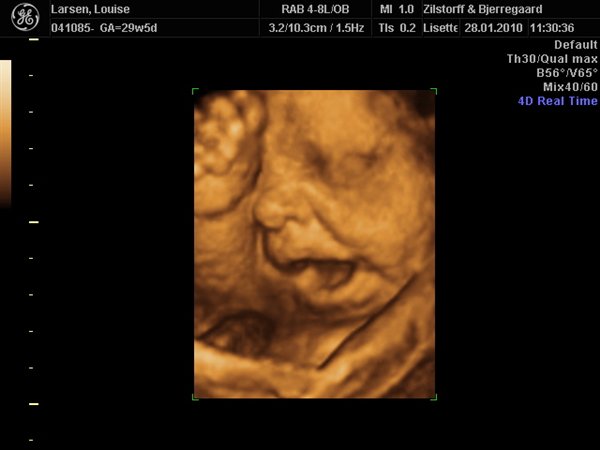

Vi har været til 3D/4D Scanning idag. Og sikke en vild oplevelse.... Har aldrig (udover min fødsel af Nicklas) prøvet noget så stort!

Her er lidt billeder: